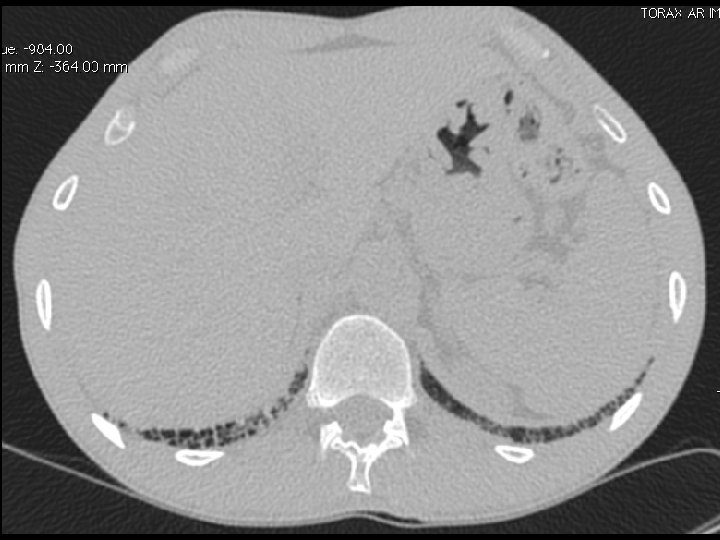

High-resolution CT scan

Subpleural, basal predominance Reticular abnormality Honeycombing with traction bronchiectasis UIPUIP Pattern

Subpleural, basal predominance Reticular abnormality Honeycombing with traction bronchiectasis Profuse micronodules UIPUIP Pattern Inconsistent with UIP Pattern